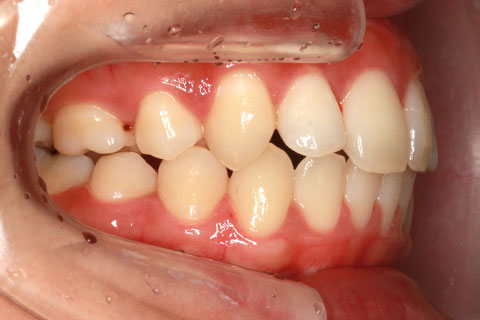

矯正期間24ヶ月

ハーフリンガル矯正4(上の歯のみ舌側矯正で治療)

治療前

治療中

治療後

- 年齢・性別

- 23歳女性

- 治療期間

- 2年0ヶ月

- 抜歯

- 上下4番抜歯

- 治療費

- 110万円

- 備考

- マルチブラケットを用いた矯正治療

- 治療内容

- 施術の副作用(リスク)

- 表側矯正と比較して、前歯のラビッティング(舌側傾斜)を起こしやすい。